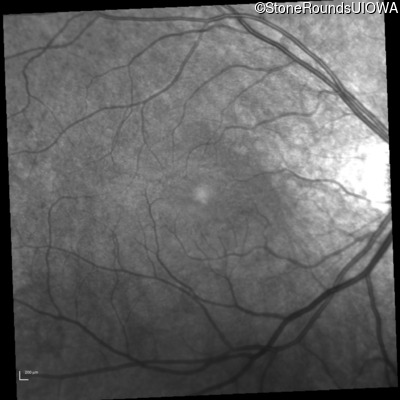

Infrared Fundus Photograph - Left - 20/50

Exemplar